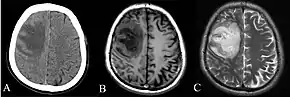

Imaging

Various imaging modalities can also help with the diagnosis of melioidosis. In acute melioidosis with the spreading of the bacteria through the bloodstream, the chest X-ray shows multifocal nodular lesions. It may also show merging nodules or cavitations. For those with acute melioidosis without the spread to the bloodstream, chest x-ray most commonly shows upper lobe consolidation or cavitations.[10] In chronic melioidosis, the slowly progressing of upper lobe consolidation of the lungs resembles tuberculosis.[10] For abscesses located in other parts of the body apart from the lungs, especially in the liver and spleen, CT scan has higher sensitivity when compared with an ultrasound scan. In liver and splenic abscesses, an ultrasound scan shows "target-like" lesions while CT scan shows "honeycomb sign" (abscess with loculations separated by thin septa) in liver abscesses.[10] For melioidosis involving the brain, MRI have higher sensitivity than a CT scan in diagnosing the lesion. MRI shows ring-enhancing lesions for brain melioidosis.[10]